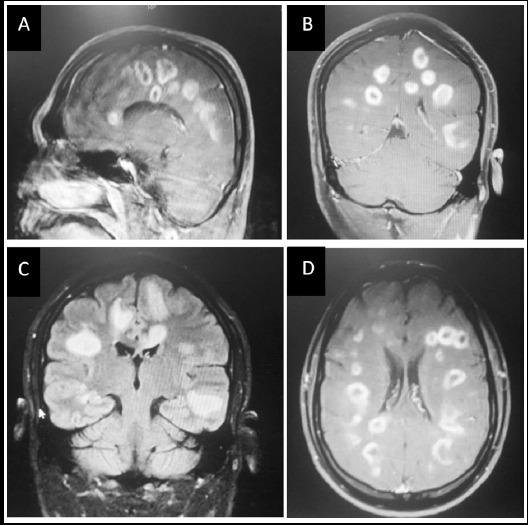

Toxoplasmosis is an obligate intracellular, food borne parasite disease with variable clinical presentation. Although the neurological presentation of toxoplasmosis in immunocompetent patients is uncommon, broad differential diagnosis should be kept in consideration when attending to similar patients. Twenty years old man with no known co-morbid conditions presented with fever and unilateral limb weakness for three weeks. It increased gradually, associated with altered level of consciousness for the last five days, diagnosed as acute toxoplasmosis. MRI Brain showed multiple ring enhancing lesions in frontal, parietal and temporal lobes. Serology for toxoplasmosis denoted raised IgM levels 36IU/mL (cut off value > 18IU/mL). This case report describes the clinical presentation and management of neurological toxoplasmosis in immunocompetent patient. Early diagnosis and prompt management can resolve the symptoms at an earlier stage.

弓形虫病是一种专性细胞内、食源性寄生虫病,临床表现多样。虽然免疫功能正常患者的弓形虫病神经学表现并不常见,但在诊治类似患者时应考虑进行广泛的鉴别诊断。一名20岁、无已知合并症的男性患者出现发热和单侧肢体无力三周。症状逐渐加重,在过去五天伴有意识水平改变,被诊断为急性弓形虫病。脑部MRI显示额叶、顶叶和颞叶有多个环形强化病灶。弓形虫病血清学检查显示IgM水平升高至36IU/mL(临界值>18IU/mL)。本病例报告描述了免疫功能正常患者神经型弓形虫病的临床表现及治疗。早期诊断和及时治疗可在更早阶段缓解症状。